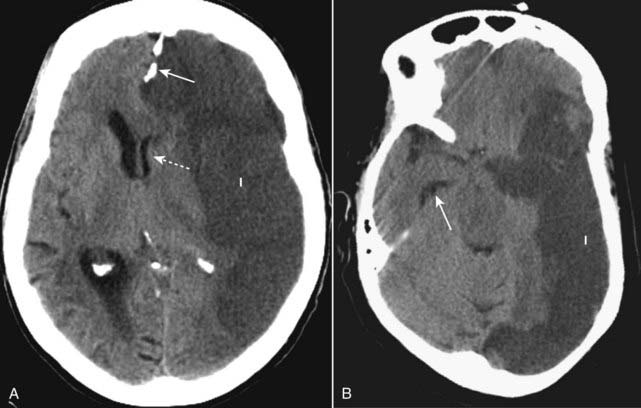

image Recognizing an acute subdural hematoma

On CT, acute subdural hematomas are crescent-shaped, extracerebral bands of high attenuation that may cross suture lines and enter the interhemispheric fissure. They do not cross the midline.

Typically, a SDH is concave inward towards the brain (epidural hematomas are convex inward) (Fig. 25-9A).

As time passes and they become subacute, or if the subdural blood is mixed with lower attenuating CSF, they may appear isointense (isodense) to the remainder of brain, in which case you should look for compressed or absent sulci or sulci displaced away from the inner table as signs of SDH (Fig. 25-9B).

Subdural collections may demonstrate a fluid-fluid level after 1 week, as the cells settle under serum.

image Chronic subdural hematoma

Chronic subdural hematomas are those present more than 3 weeks after injury.

Chronic subdural hematomas are usually low density compared to the remainder of the brain (Fig. 25-9C).

image

Figure 25-9 Acute, isodense, and chronic subdural hematomas.

A, There is a crescent-shaped band of high-density blood concave inward towards the brain (solid white arrow). Mass effect is present with herniation of the brain as indicated by the dilated contralateral temporal horn (dotted white arrow). B, As they become subacute, subdural hematomas become less dense and may be the same density (isodense) as the normal brain tissue (solid white arrow). You can recognize an isodense subdural by the unilateral absence or displacement of the sulci away from the inner table of the skull compared to the normal opposite side (solid black arrow). C, Chronic subdural hematomas (more than 3 weeks old) are usually of low density (solid white arrow) compared to the remainder if the brain. There is still mass effect demonstrated by displacement of the interhemispheric fissure (dotted white arrow) and compression of the lateral ventricle.